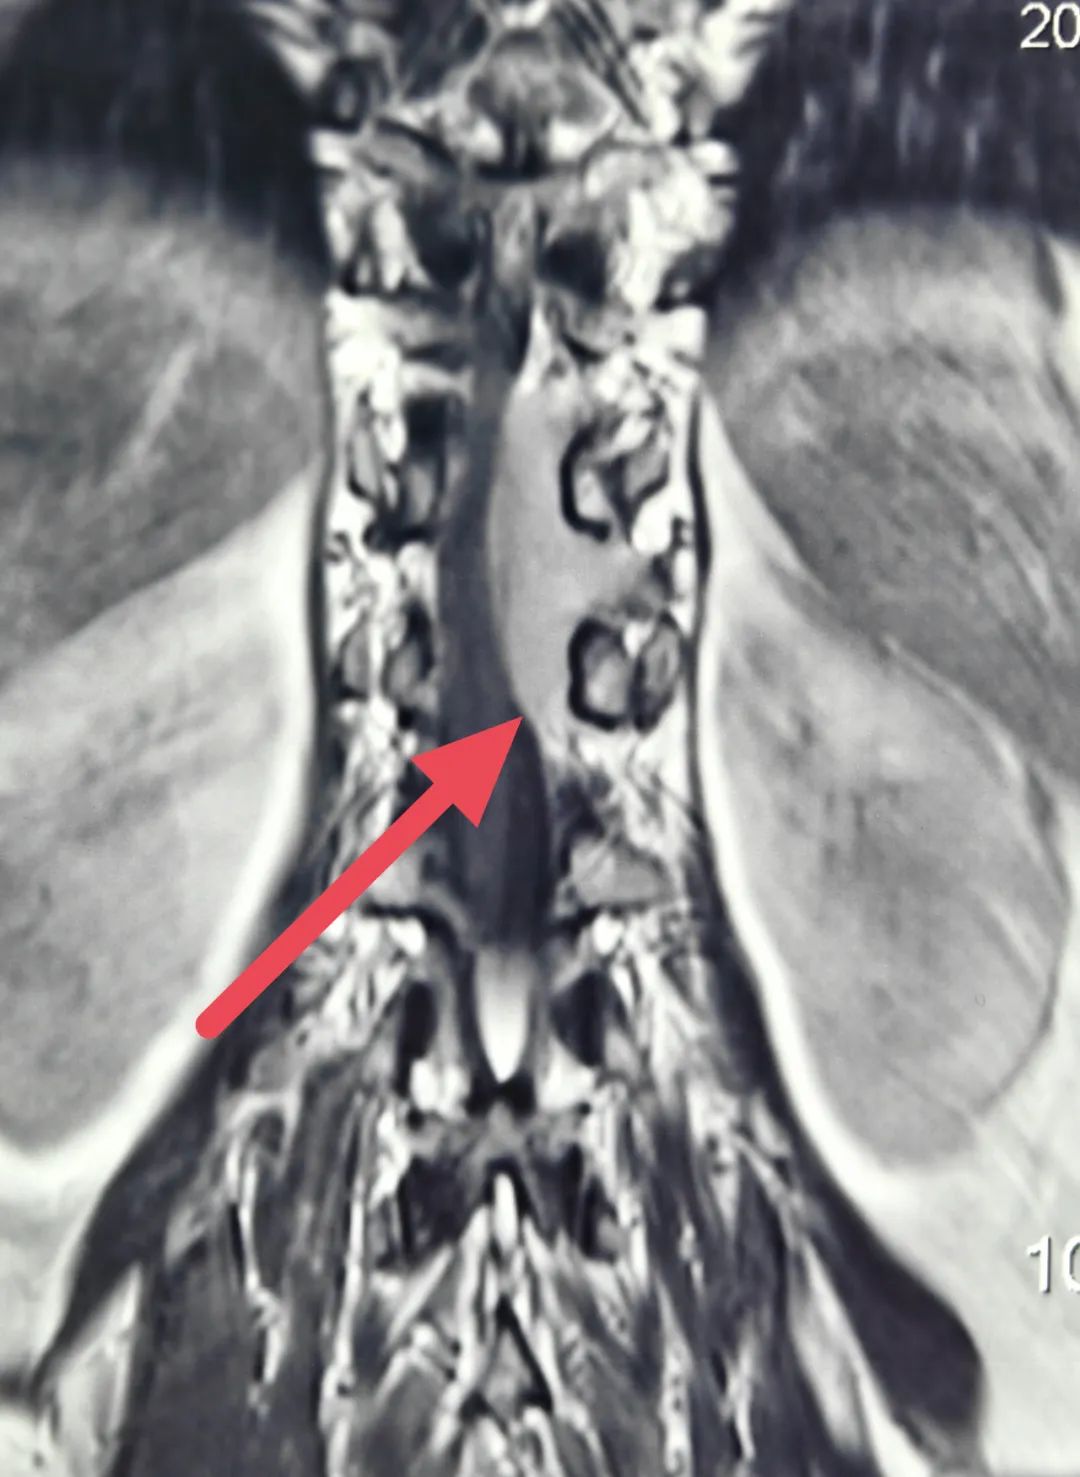

患者女,53岁,主因“胸腰背部疼痛不适1年加重伴双下肢无力2月”入院。患者1年前开始出现胸腰背部疼痛,以为是腰肌劳损,自行按摩理疗稍缓解后就没再理会。近两月来,患者疼痛进行性加重,疼痛评分8分,已严重影响行走,来院时已无法独立行走,需搀扶行走,行走似踩棉花感,大便便秘,小便费力。入院查体提示下肢肌力3级,病理征阳性。磁共振提示胸腰段巨大肿瘤包裹脊髓,且血供丰富。经过西安市红会医院神经外科赵东升主任仔细阅片分析病情后,决定手术切除肿瘤。

术前增强磁共振